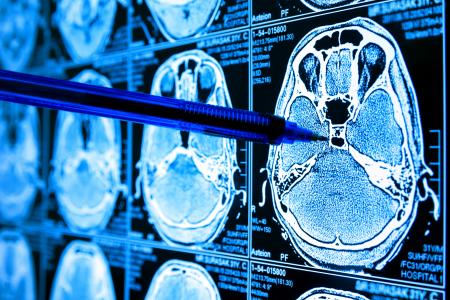

GLIOBLASTOME : Les promesses d’un médicament de l’Alzheimer

Un médicament expérimenté dans la maladie d'Alzheimer pourrait être prometteur pour le traitement du glioblastome, révèle cette équipe de la Cleveland Clinic : il s’agit du verubecestat, conçu pour onçu pour empêcher le cerveau de produire une protéine caractéristique de l’Alzheimer, la bêta amyloïde, et la molécule réduit ici sur des modèles précliniques la progression du glioblastome. De premiers résultats, très encourageants, publiés dans la revue Nature Cancer.